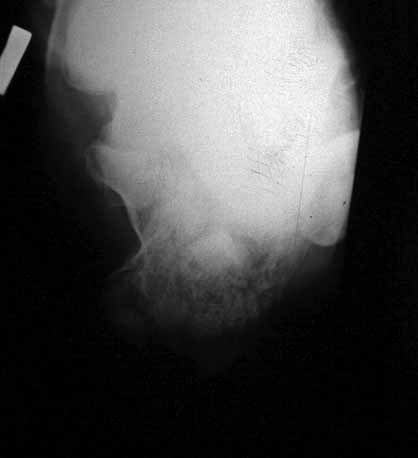

КТ перелома пяточной кости

в замешательство.Прилагаю снимки со дня поступления, августовские пациентом не

представлены.С благодарностью примем советы коллег.